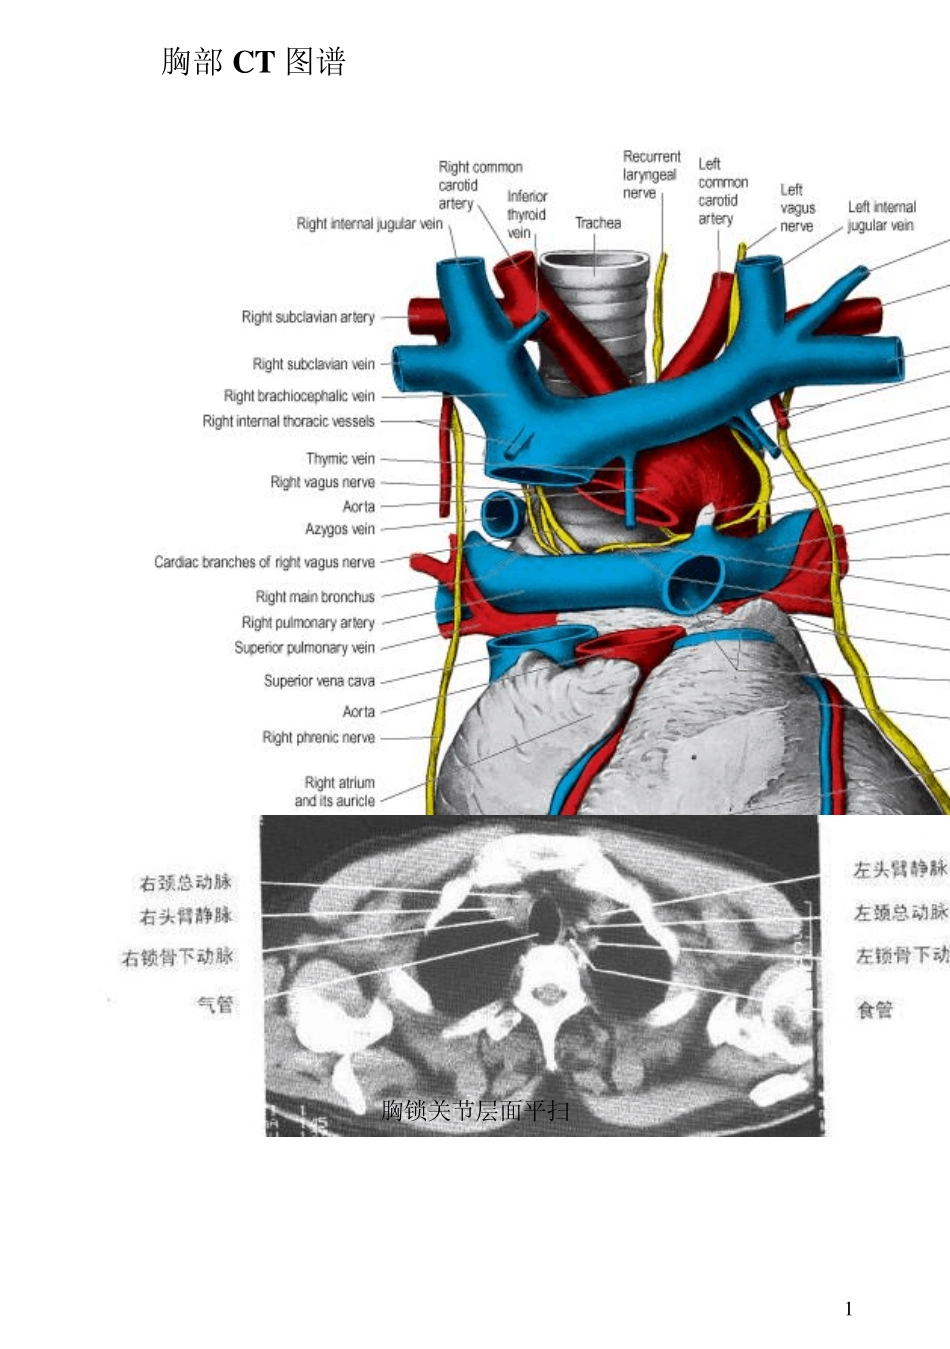

胸部CT图谱

1 胸部CT 图谱 胸锁关节层面平扫 2 胸锁关节层面增强 主动脉弓上层面 3 主动脉弓层面气管分叉层面平扫气管分叉层面增强 肺动脉干与右肺动脉层面平扫 4 左心房层面平扫左心房层面增强左、右心房层面增强 5 四腔心层面平扫心室层面平扫 6 7 8 9